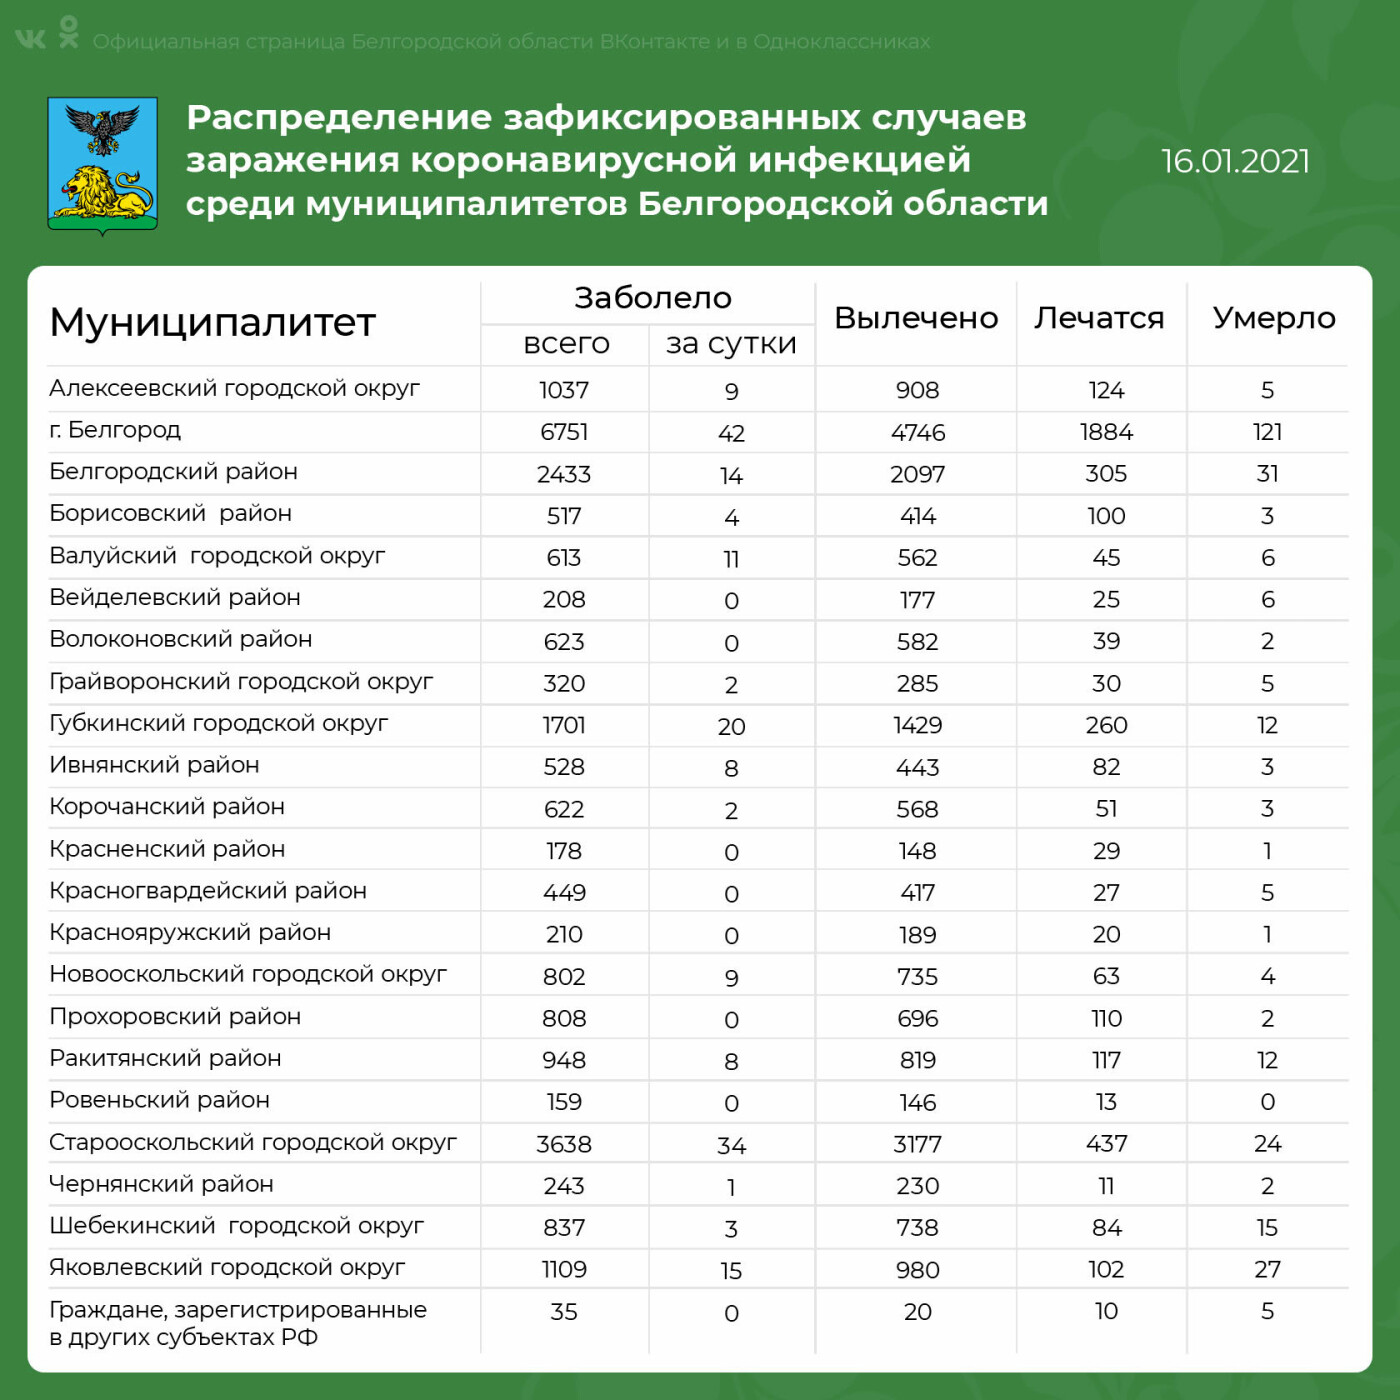

16 января. В Белгородской области от коронавируса умерли ещё два пациента

Как рассказали в региональном оперативном штабе по борьбе с распространением инфекции, за последние сутки жертвами ковида стали ещё два жителя региона.

Одному из умерших, жителю Яковлевского городского округа, было всего 39 лет. Второму, жителю Белгорода, было 64.Оба они лечились в ковид-госпитале на базе детской областной больницы.

Вот важнейшие актуальные показатели развития эпидемической ситуации.

● Заразившихся за сутки – 182.

● Всего инфицированных – 24 769.

● Умерших – 295.

● Лежат с коронавирусом в больницах – 994.

● Подключены к аппаратам искусственной вентиляции лёгких – 134.

● Выздоровело – 20 506.